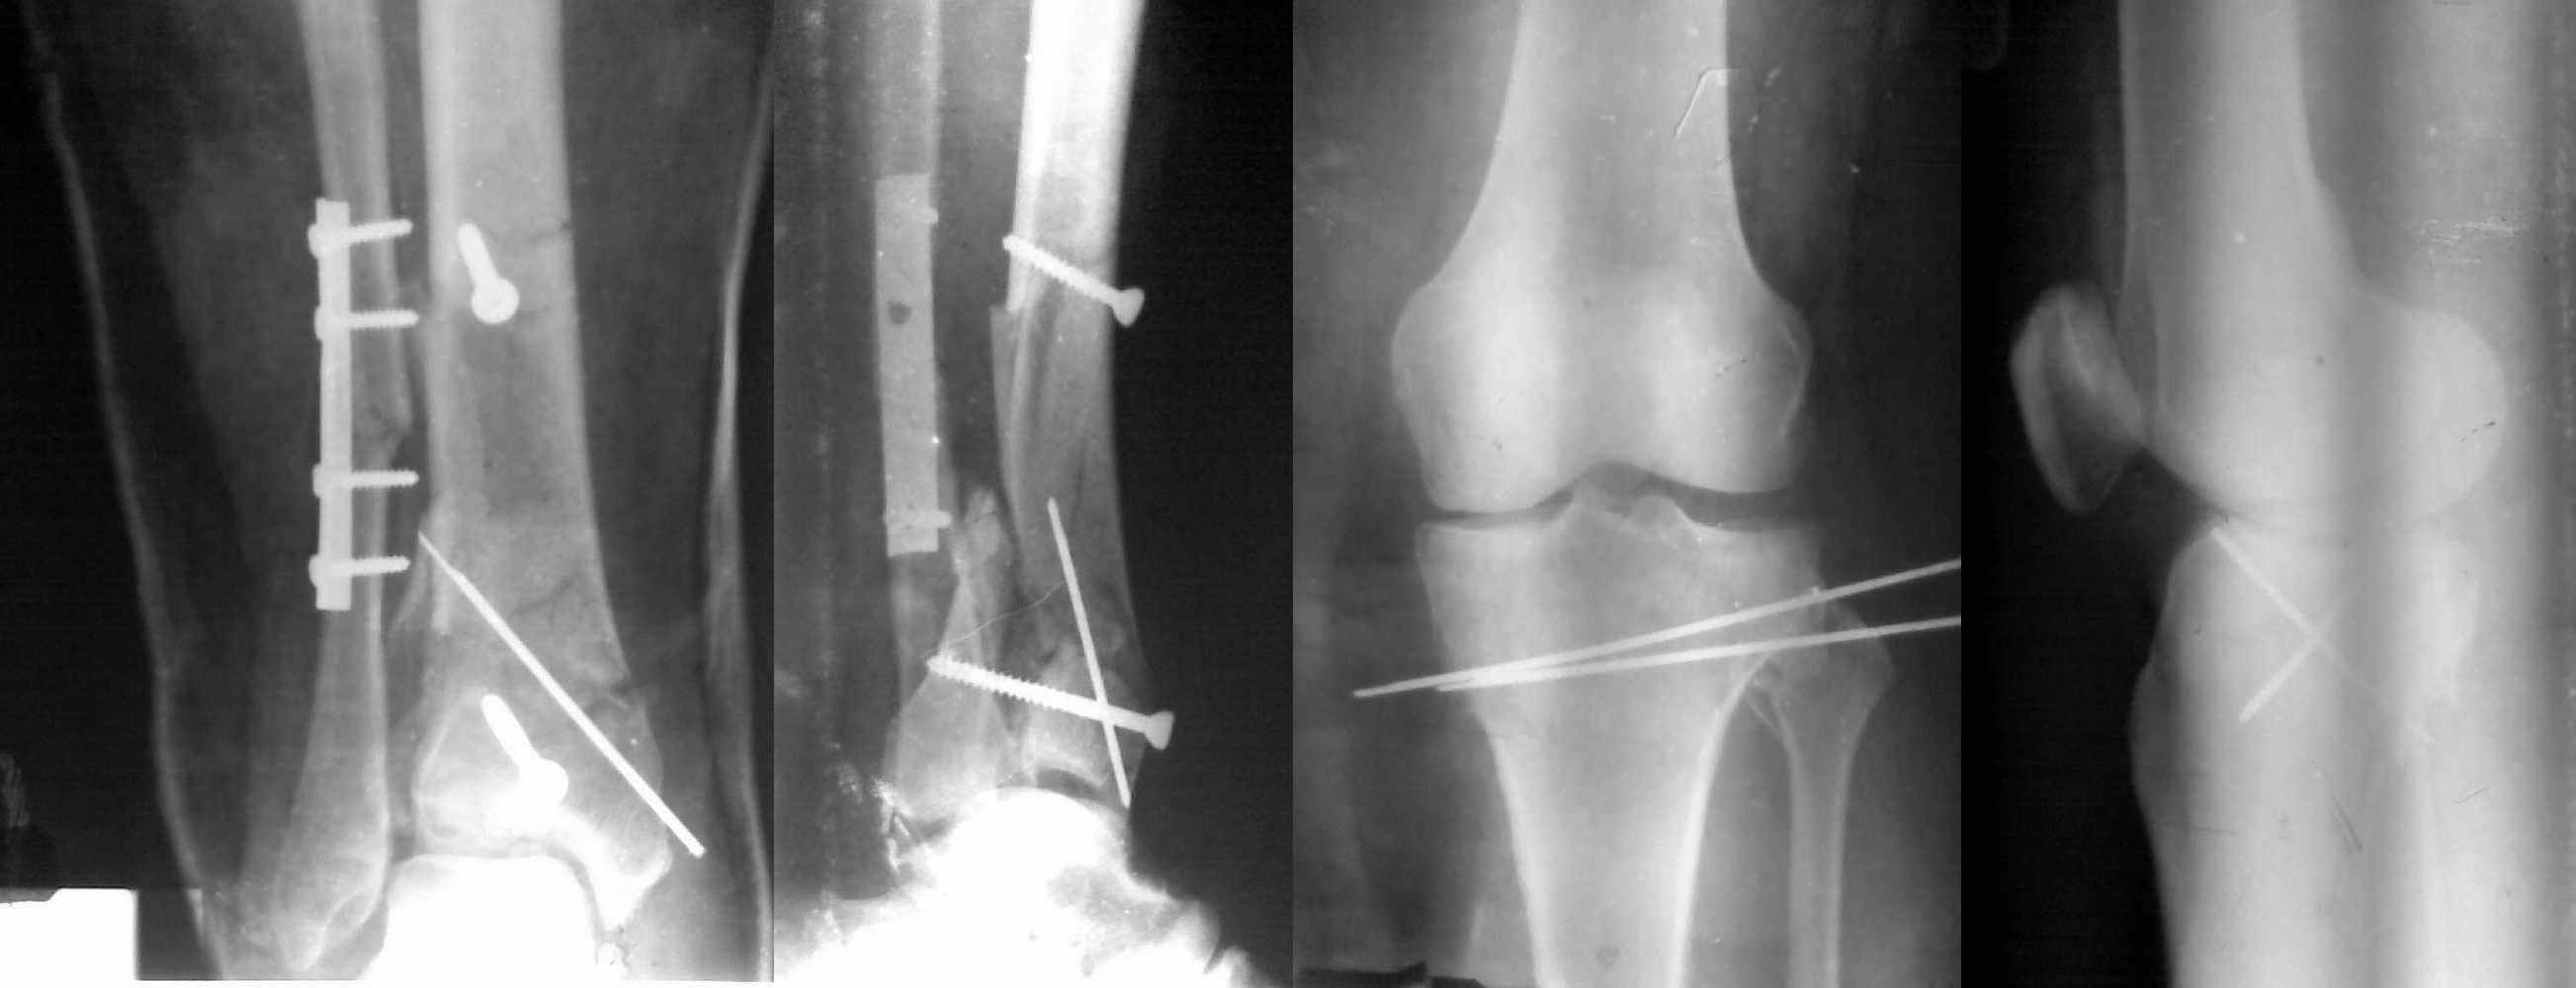

Пациентки прооперирована, результат чего на снимках. Выполнена открытая репозиция костей правой голени, синтез малоберцевой пластиной, б/берцевой винтами, имеющиеся фиксаторы не подходили, было принято решение репонировать отломки, синтез винтами, гипсовая повязка.

В данный момент локально отёк тыла стопы незначительный, двигательня функция сохранена, ограничена болевым синдромом. Пульсация артерий ослаблена, соответствует левой ноге. Рана - в области границы с пузырём область некроза 2.5*2 см, сухой, не увеличивается, под ним чувствительность сохранена. Чувствительность по всей поверхности кожи в норме, гипоестезия пальцев, при чём варьирует от нормальной, до почти анестезии в течении дня.

Мыщелок левой б/б кости репонирован закрыто, на контрольной рентгенограмме репозиция удовлетворительная, фиксировано спицами. гипсовая повязка.

Репозиция внутрисуставных переломов неудовлетворительная и не адекватна.

Сделайте снимок голеностопа контрлатеральной стороны, перенесите контур сустава на кальку и наложите её на свои послеоперационные Ргграммы - вам станет ясно что нужно сделать и какого стояния отломков достичь. Аналогичный

сценарий и для перелома наружного мыщелка б.б.- передний фрагмент стоит на месте, а задний не репонирован - в таком положении оставлять фрагменты нельзя, суставная поверхность должна быть реконструирована.

В лечении переломов пилона восстановление длины малоберцовой является индикатором и ориентиром для успешного лечения. Первый этап восстановления по длине не удался, малоберцовая остается короткой, и репозиция суставной поверхности осталась неудовлетворительной. Длина передней колонны не восстановлена, а в дистальном фрагменте имеется флексия. Оставлена без внимания потеря кости в метафизе. Шурупы 4.5 мм будут выступать после спадения отека, и возможно будут причиной мягкотканого осложнения в гипсе.